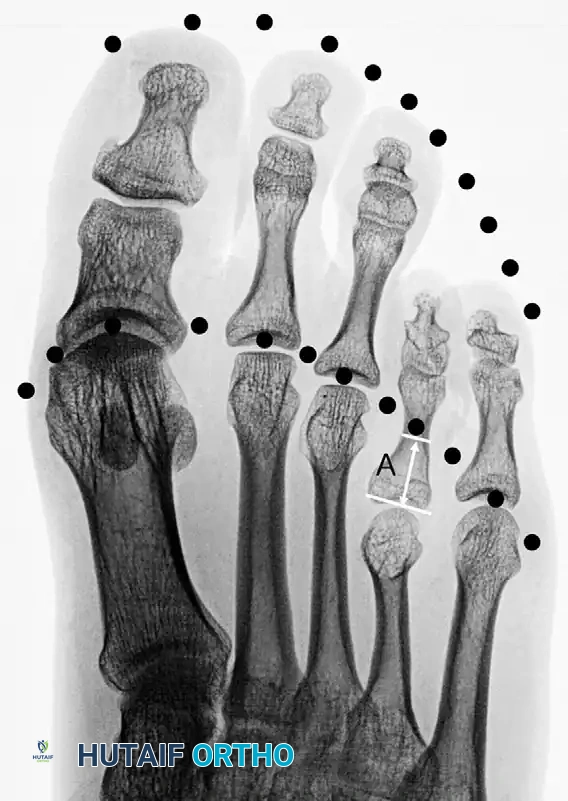

Radiographic evaluation requires standard weight-bearing anteroposterior (AP), lateral, and oblique views of the foot. On the AP radiograph, the normal metatarsal parabola can be traced to identify the exact degree of shortening.

When brachymetatarsia is present, this parabolic arc is severely disrupted. The distance required to restore the affected metatarsal head to the ideal parabola dictates the surgical lengthening goal.

Figure 2: Disruption of the normal parabolic arc associated with brachymetatarsia of the first metatarsal.

Figure 3: Disruption with brachymetatarsia of the fourth metatarsal. The distance marked “A” represents the precise length needed to obtain an ideal parabola.

Clinical Pearl: When calculating the required lengthening distance, always account for the soft tissue envelope. Lengthening a metatarsal by more than 40% of its original length significantly increases the risk of neurovascular compromise, severe joint stiffness, and MTP joint subluxation.